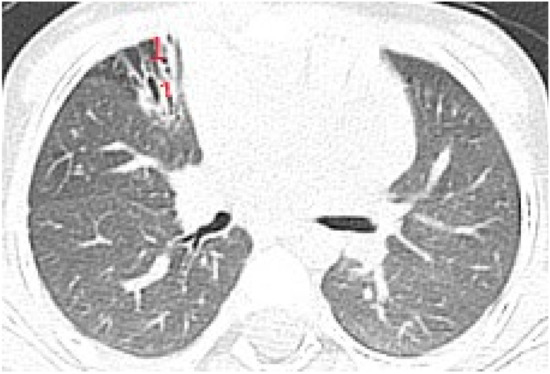

In patients with important structural lung damage (Figure 7), quantified as severe disease, expressed by a CT score > 66, the correlation was strong (rs = 0.83), with statistical significance (p = 0.002).

The assessment of LUS sensitivity and specificity in bronchiectasis detection varied with the form of bronchiectasis: for cylindrical bronchiectasis(Figure 8A,B), LUS Se = 77.7%, Sp = 9%, PPV = 80.7%, and NPV = 76.9%, while for saccular bronchiectasis (Figure 7), a moderate Se = 68.4%, with good Sp = 94.9%, PPV = 88.8%, and NPV = 94.7% were found.

Figure 7. (A) LUS: coalescent B lines, erased A profile, loss of aeration, left hemithorax. (B) LUS image with subpleural consolidations, coalescent B lines, and left hemithorax. (C) CT scan of the same patients: (1) varicose bronchiectasis with middle 1/3 of lung extended and moderate bronchial wall thickening; (2) saccular bronchiectasis with mild and moderate wall thickening; and (3) zones with increased attenuation of pulmonary parenchyma (alveolar infiltrates).

Figure 8. (A) CT scan: cylindrical bronchiectasis with mucus plugs (B) LUS: A lines, normal LUS aspect, score = 0.